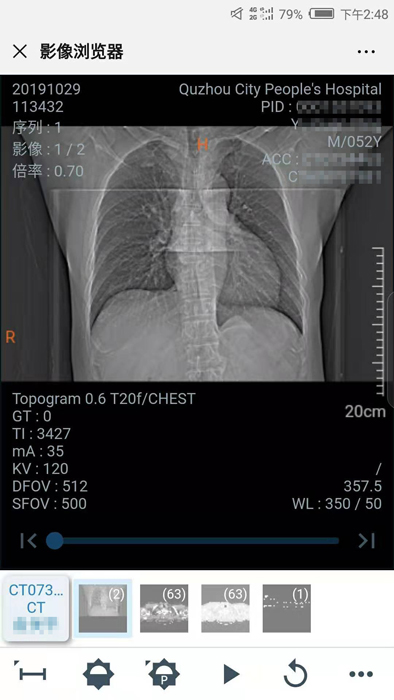

10月29日晚,我院向住院患者推行數(shù)字影像服務,云膠片正式上線!點點手機就能查看片子不限次數(shù)瀏覽影像……方便、省錢、精準、環(huán)保,“云影像”服務平臺讓您看病更省心。

10月30日,住院患者俞先生收到一條短信提醒“【云影像】衢州市人民醫(yī)院提醒您,俞先生的CT報告已完成……”俞先生隨即點擊手機上的瀏覽鏈接,輸入身份證后六位,驗證完成,短短幾秒鐘,躺在病床上也能查看到自己的CT電子報告和影像,俞先生直呼神奇。

“醫(yī)院面向住院患者全面推行檢查檢驗結果電子化,互認共享,全面提供網(wǎng)上查詢、移動推送等服務,‘云影像’平臺的運行就是深化‘最多跑一次’改革要求的又一新舉措?!贬t(yī)院信息處工作人員介紹,“ ‘云影像’是儲存在云端的病人醫(yī)學影像檢查信息,包括檢查報告、電子膠片及供專業(yè)影像科醫(yī)生診斷瀏覽的全部醫(yī)學數(shù)字原始影像。放射檢查報告完成后,醫(yī)院會同步發(fā)送提醒短信到患者的手機上,只要點擊短信上的鏈接就可第一時間獲取‘云影像’及報告。使用‘云影像’查看檢查報告,解決了排隊取片、復診帶片的煩惱,縮短了就醫(yī)時間,讓老百姓看病得到實實在在的方便?!?